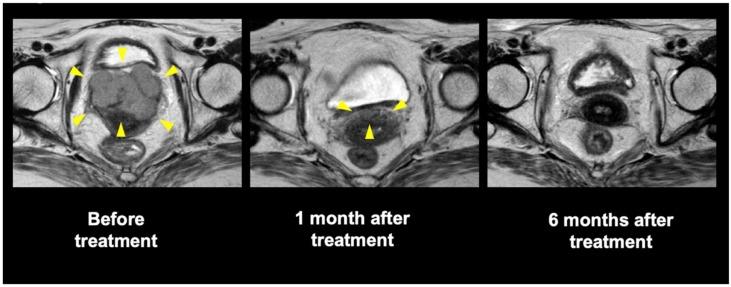

Surgical resection is considered a standard therapy for malignant melanoma (MM). However, it has not yet been established as an optimal treatment strategy for gynecological MMs, particularly owing to their very low incidence rates. We retrospectively analyzed clinical outcomes of carbon-ion radiotherapy (C-ion RT) for gynecological MMs. The eligibility criterion was the presence of histologically confirmed gynecological MM. Patients with pelvic or inguinal lymph node metastases were included, while those with distant metastases were excluded. The pelvic and inguinal lymph node regions were irradiated with up to 36 gray relative biological effectiveness (Gy (RBE)) followed by a gross tumor volume boost of up to 57.6 Gy (RBE) or 64 Gy (RBE) in 16 fractions over 4 weeks. Thirty-seven patients (median age: 71 years) were examined. In total, 22 patients had vaginal tumors, 12 had vulval tumors, and 3 had cervical uterine tumors. The median follow-up periods were 23 months (range: 5-103 months) for all patients and 53 months (range: 16-103 months) for survivors. Thirty of 37 patients (81%) achieved complete tumor disappearance. The 2-year local control, overall survival, and progression-free survival rates were 71%, 53%, and 29%, respectively. C-ion RT may be a definitive treatment option for patients with gynecological MM.